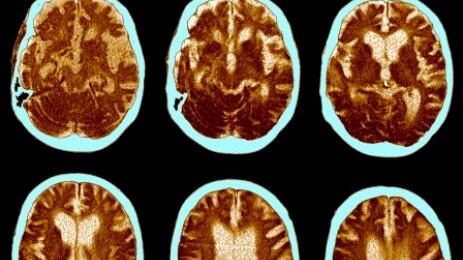

Una reciente investigación científica descubrió puntos relevantes para comprender el proceso del Alzheimer en el cerebro. Esta enfermedad es la perdida progresiva de la memoria, es la forma más común de demencia a nivel mundial y hasta ahora la evidencia médica no era suficiente para reconocer su funcionamiento precisamente.

El grupo de investigadores de la Universidad de Cambridge halló pruebas de que el Alzheimer no empieza en un punto fijo del cerebro para expandirse y matar células, sino que comienza en varias regiones del órgano. A través de la producción de grupos de proteína tóxica, mata las células, lo que produce el deterioro cognitivo, según los resultados de la investigación.

Para lograr estos hallazgos, los científicos utilizaron muestras de pacientes con Alzheimer ya fallecidos. Se los comparó con análisis PET de pacientes vivos, algunas con un deterioro cognitivo leve y otros con la enfermedad avanzado. Esto se hizo para seguir el paso de la agregación de proteína tau.

Esta y otra más, la beta-amiloide, son proteínas clave que se atascan en agregados, producen la muerte de las células y que el cerebro se encoja. Así se produce la perdida de memoria, dificultas para realizar actividades diarias e incluso cambios en la personalidad. La escala en la que se mide el grado de Alzheimer es denominada “Escala Braak”.

Los investigadores descubrieron que toma 35 años pasar de la etapa tres (con síntomas leves) hasta la seis, es decir, la más avanzada. Anteriormente la ciencia se había basado en estudios del cerebro de especies animales para entender la enfermedad, por su complejidad de diagnóstico al poder ser confirmada únicamente al analizar el tejido cerebral del paciente después de su muerte.